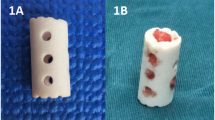

The strut body is composed of a cylindrical body and an endplate with unique contact surfaces at both ends. The cylindrical main body is hollow (the same as before), with two small circular holes in the front and back and three small circular holes in the lateral sides. The novel design of the cylindrical body is also hollow, the front and rear four small circular holes are closed, and the left and right three small circular holes are changed to one lateral hole to further expand the contact surface between the strut body and the vertebral body to promote bone graft fusion. According to the length and width of the vertebral bodies, different models are created to show the intraoperative placement of the newly optimized strut (Figs. 1, 2).

ACCF is widely used in treating cervical diseases such as degeneration, trauma and tumours because of its advantages, such as a large surgical field, easy operation, thorough decompression and accurate curative effect. TMCs are commonly used in reconstruction, and the long-term follow-up results show that there are still some defects, such as subsidence leading to recurrent neck pain, neurological impairment, or even failure of internal fixation [1, 2]. The n-HA/PA66 invented and developed by our team is a new nano-biomimetic material. After frequent clinical applications, the initial and long-term follow-up showed that the fusion rate and clinical results of the n-HA/PA66 strut were satisfactory. However, we found that part of the strut subsided, a gap appeared in the cylinder area on radiograph, and there was no bone graft fusion or bone graft fusion around the cylinder [1,2,3]. Based on the follow-up results, the design of the n-HA/PA66 strut still needs to be improved to achieve better bone fusion. We further improved the design of the n-HA/PA66 strut. Therefore, based on old biological materials, this study designed a new face of a strut. The columnar body of the new strut body is hollow, similar to the old strut body, and the lateral small round holes are replaced with a rectangular lateral hole to further expand the contact surface between the strut body and the vertebral body to achieve better biomechanical performance and to better distribute stress, avoiding postoperative subsidence and increasing the biomechanical stability at the surgical level [4,5,6,7].